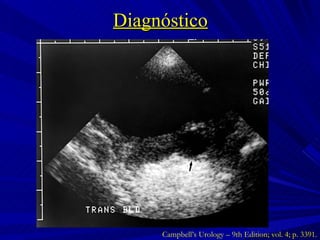

Diagnóstico Campbell’s Urology – 9th Edition; vol. 4; p. 3391.

Diagnóstico Campbell’s Urology – 9th Edition; vol. 4; p. 3393.